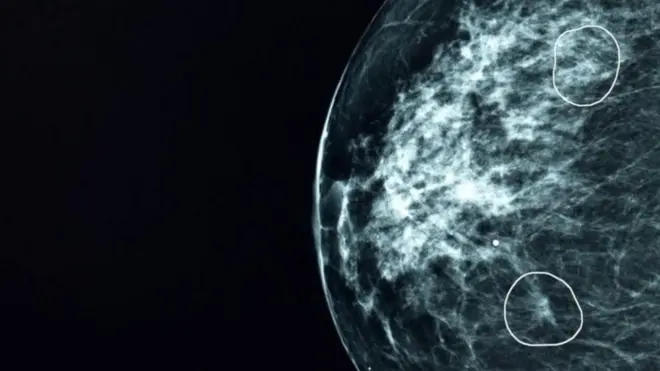

Cependant, chaque jour, nos cellules subissent des dommages à leur ADN (le matériel génétique des cellules) dus à diverses sources, telles que les rayons ultraviolets, l'exposition à des produits chimiques, et même notre propre métabolisme cellulaire. Ces dommages cellulaires contribuent au vieillissement et au risque de cancers, comme le mélanome, un type de cancer de la peau.

Cette nouvelle étude met en lumière ce qui se produit lorsque les cellules souches mélanocytaires, situées au cœur du follicule pileux, subissent des dommages à l'ADN, notamment un type de dommage appelé cassure double brin.

Cette recherche suggère que le devenir des cellules souches de mélanocytes semble dépendre à la fois du type spécifique de dommages qu'elles subissent et des signaux moléculaires présents dans leur microenvironnement. Les facteurs de stress, tels que les substances chimiques ou les rayons UV, qui provoquent la rupture des chaînes d'ADN des cellules, entraînent également l'autodestruction des cellules souches de mélanocytes. Ce même processus est à l'origine des cheveux gris.

Mais sous l'influence de cellules cancéreuses, ces cellules souches de mélanocytes endommagées persistent, créant ainsi des germes à partir desquels le mélanome peut se développer. Les scientifiques décrivent cette dynamique comme des "destins antagonistes" — dans lesquels une même population de cellules souches peut suivre deux voies radicalement différentes, selon les circonstances.

Il est important de souligner que ces découvertes réinterprètent les cheveux gris et le mélanome non pas comme des phénomènes sans lien apparent, mais comme les deux facettes d'un processus ancestral visant à équilibrer le renouvellement tissulaire et à prévenir le cancer. Le vieillissement n'est pas, en soi, une protection contre le cancer, mais plutôt un effet secondaire d'un processus protecteur qui élimine les cellules à risque.

En revanche, lorsque les mécanismes de contrôle sont défaillants ou perturbés par des agents cancérigènes, le risque de cancer augmente. Cette nouvelle compréhension pourrait également expliquer pourquoi nous sommes plus susceptibles de développer un cancer en vieillissant.